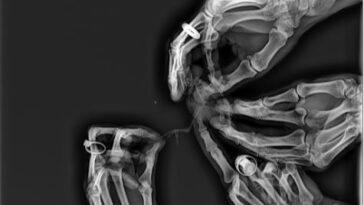

6. Normální ruka / ruka po výbuchu ohňostroje.

Co dodat,… ohňostroje vážně nejsou sranda.

Normální ruka / ruka po výbuchu ohňostroje

od u/Dressa1996 v medizzy